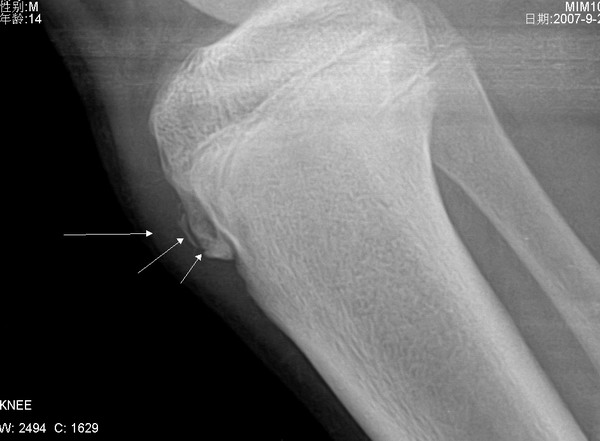

胫骨结节 男 14岁 平时常参加体育活动 右侧胫骨结节处按压或活动时疼痛.

本病1、发病年龄

2、膑韧带下端增厚肿胀

3、胫骨结节骨骺前缘见骨质缺损

4、胫骨结节前方断续钙化

5、局部疼痛

6、非滑膜部位

均支持胫骨结节骨软骨病(奥许氏病)以上为个人意见,仅供参考。